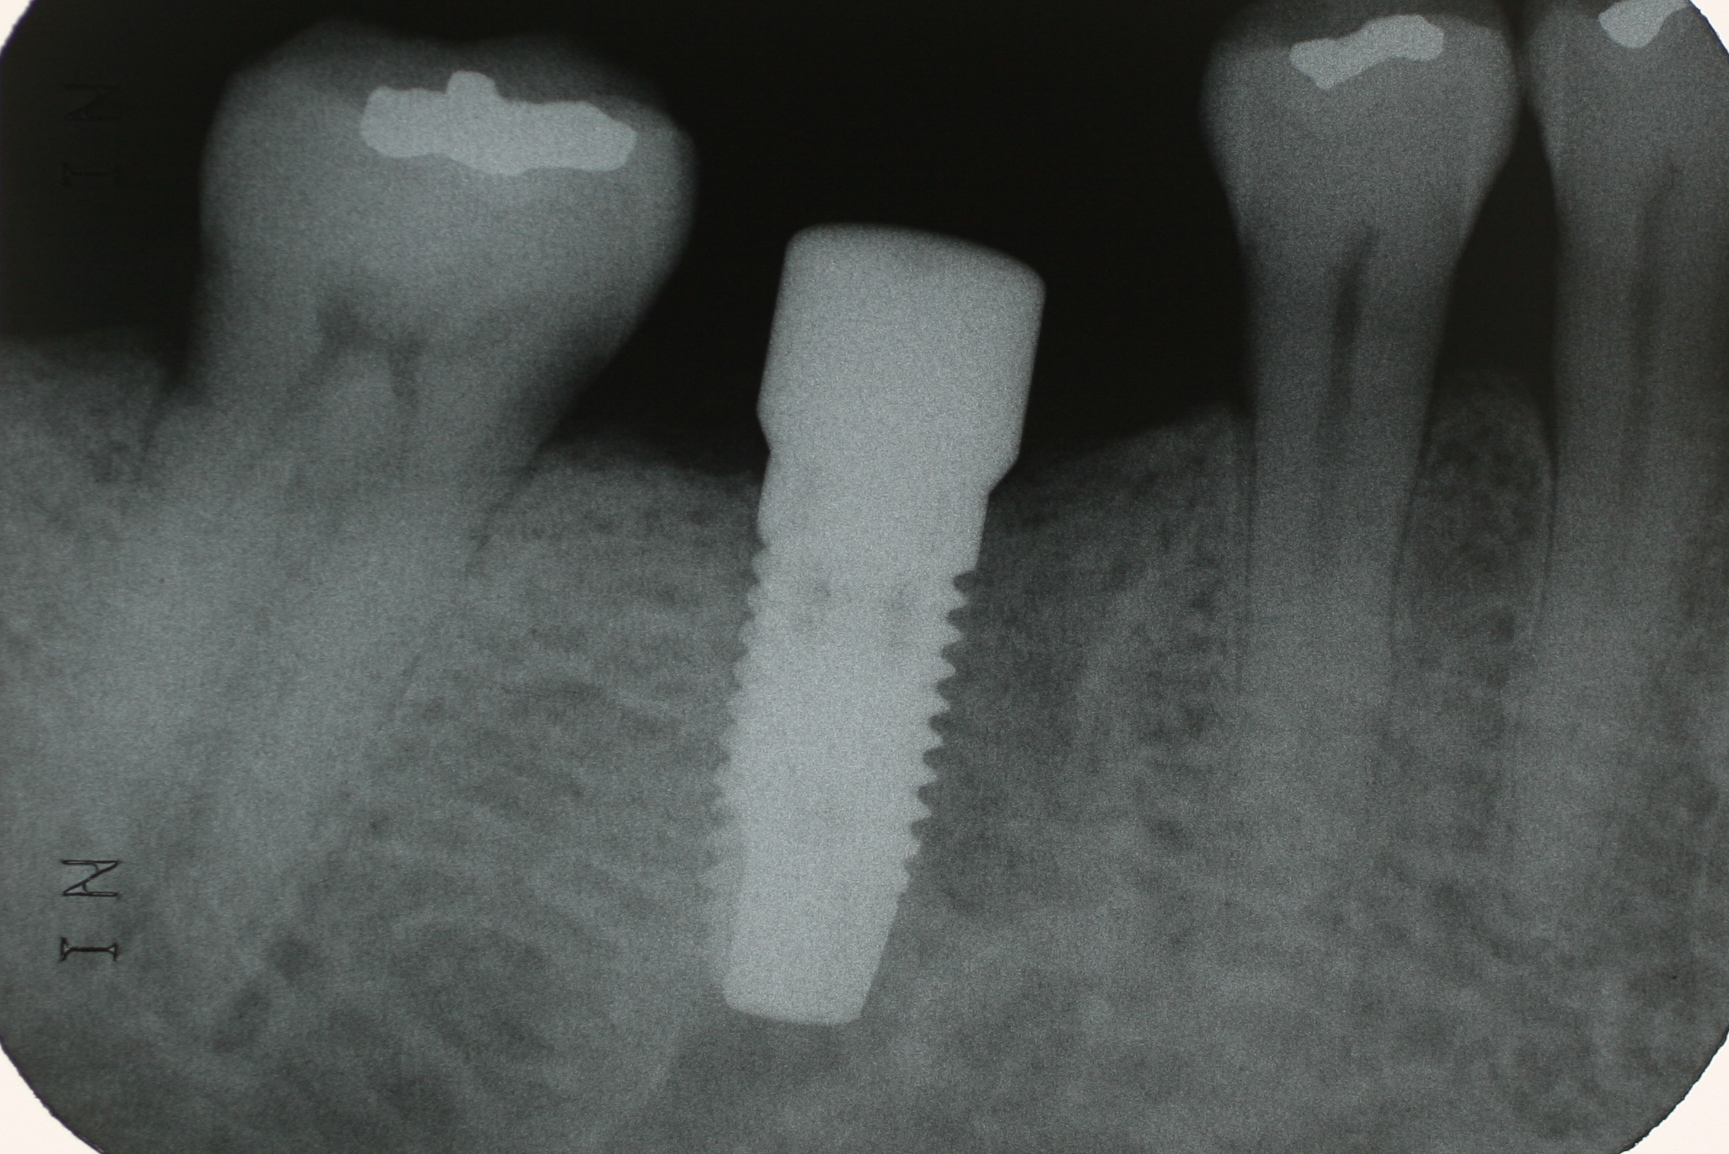

他院で抜いてもらった左下の奥歯の所(黄矢印)。痩せてしまって骨幅が少ない(黄点線)ので、インプラントは簡単ではありません。 インプラントが入る場所を3次元的にガイドするマウスピース(緑色)を装着し、Ti Ultra インプラント(青い点線から先の部分)をガイドスリーブ(黄色)に正確に入れて行きます。 CCという最新の接合様式(青)を持った陽極酸化処理で金色に輝くTi Ultra インプラント(黄色)が寸分違わず計画した3次元的位置に収まりました。この後自家骨とサイトランスグラニュールという人工骨を露出したインプラント周囲(黄色)に移植し、サイトランスエラシールドという吸収性膜で被覆して手術を完了しました。 いかがでした? 今回のブログで、読者の皆様のインプラントに対する理解が少しでも深まれば幸いです。

今回は ZIMMER 社のインプラントを使いました。非常に細く短いインプラントをピンポイントで埋入します。術者の経験が結果を左右するデリケートな手術です。 今日のオペは実質30分程で終了しました。ただ、医科の内視鏡手術と同様に、通常のオペの経験を充分に積んだ歯科医師でなければ難しい部分が多いなと感じました。